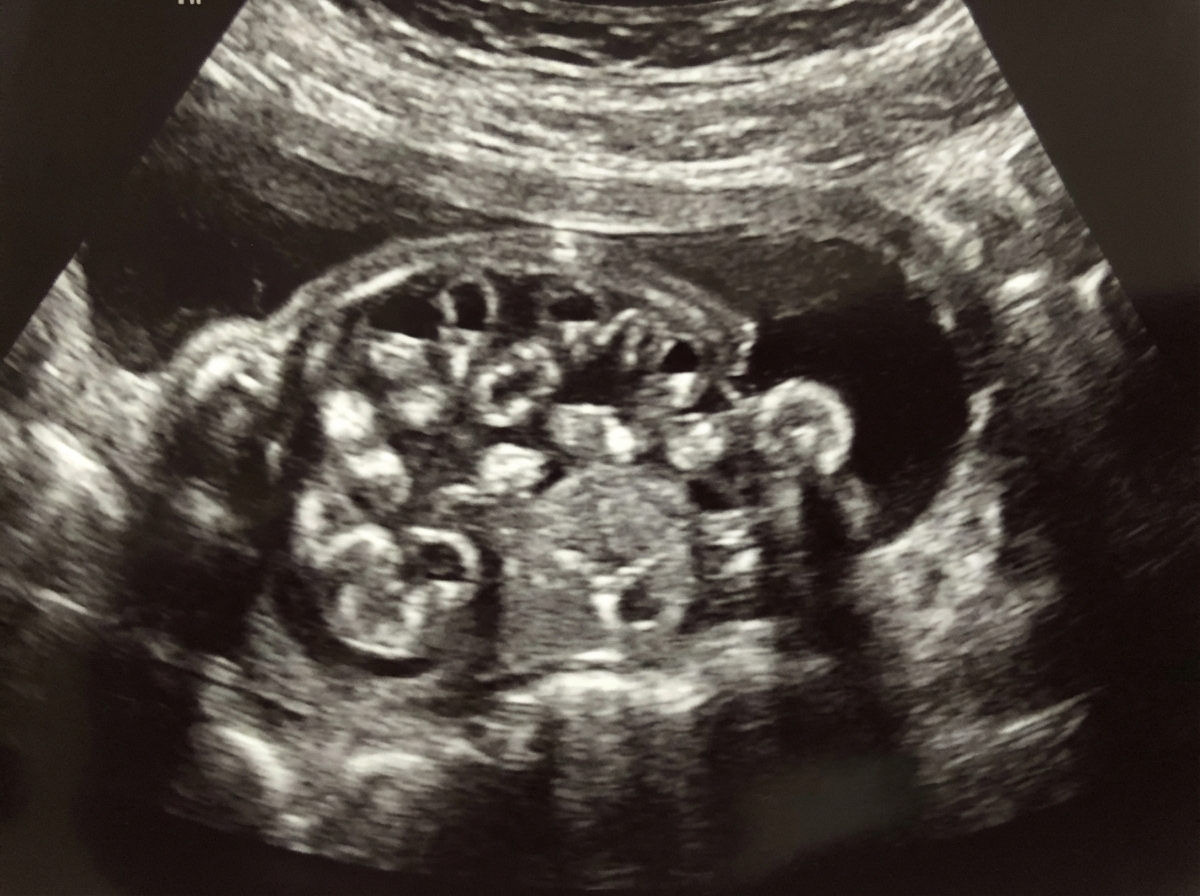

A 23-year-old woman, gravida 2, para 1, at 26 weeks gestation comes to the physician for a routine prenatal visit. Physical examination shows a uterus consistent in size with a 26-week gestation. Fetal ultrasonography shows a male fetus with a thick band constricting the right lower arm; the limb distal to the constrictive band cannot be visualized. The most likely condition is an example of which of the following embryological abnormalities?

A 19-year-old woman, gravida 1, para 0, at 21 weeks’ gestation comes to the physician for a follow-up prenatal visit. At her previous appointment, her serum α-fetoprotein concentration was elevated. She had smoked 1 pack of cigarettes daily for 3 years but quit at 6 weeks' gestation. Examination shows a uterus consistent in size with a 21-week gestation. Ultrasonography shows fetal viscera suspended freely into the amniotic cavity. Which of the following is the most likely diagnosis?